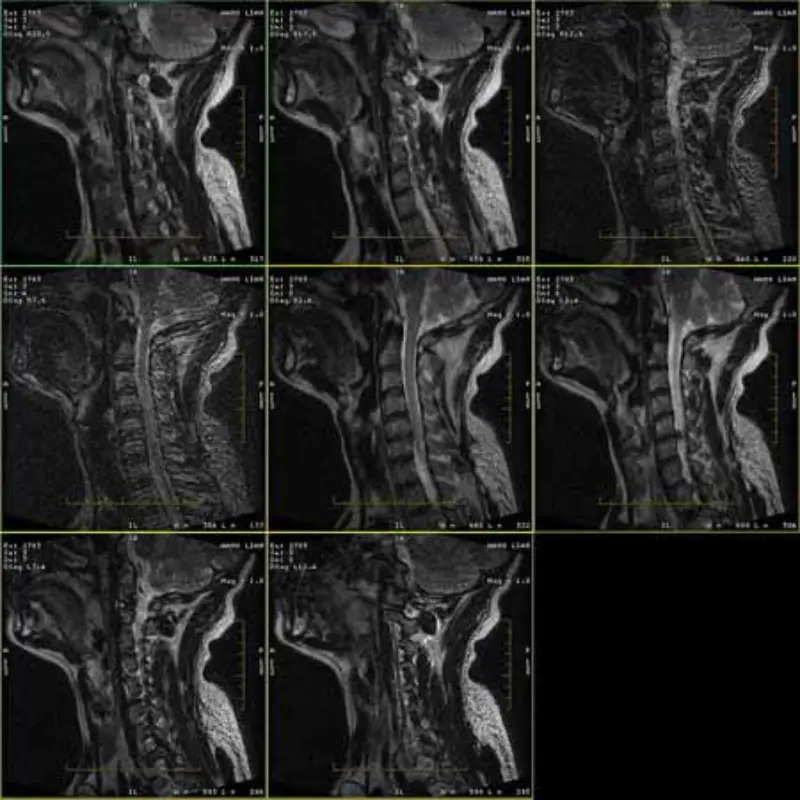

Az FRFSE és GRE protokollok képei szellemképesek, és néha alacsony SNR-képek jelennek meg egy sorozatban. De az SE protokoll képei normálisak.

Kérjük, nézze meg a csatolt képeket.